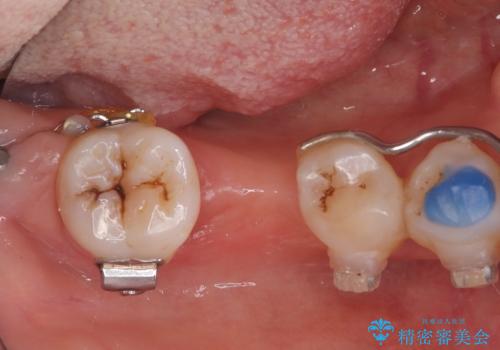

- 右下奥歯の不安定な状態を主訴にご来院されました。精密検査の結果、右下5番の歯周病が進行しており、歯周組織の再生治療が必要と判明。また、その奥にある7番の歯が傾いていたため、6番の部分にインプラントを入れる前に、部分矯正で7番を理想的な位置に起こす計画を立案しました。これら一連の治療を経て、最後に失われた6番の部分にインプラントを埋入し、機能的な咬み合わせを再建することを目指しました。

右下5番の歯周組織再生治療: まず、歯周病が進行していた5番に対して、再生療法を行いました。これにより、失われた骨や歯周組織の回復を促し、歯を安定させることができました。